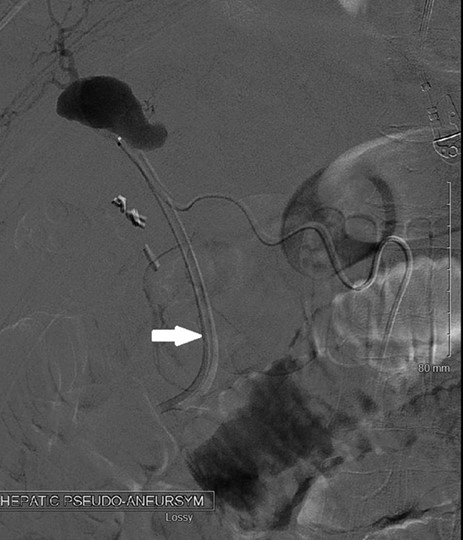

Hemobilia, as seen on this patient’s ERCP, can result from a variety of pathologies though is usually a result of instrumentation of the biliary tract and injury to a nearby vessel [2]. In this case, a hepatic artery pseudoaneurysm formed during his severe cholecystitis, as seen on his MRCP at presentation (Fig. 1). MRI of the abdomen with MRI cholangiogram demonstrated cholelithiasis and pericholecystic edema consistent with cholecystitis. In addition, a 2.6 cm pseudoaneurysm was identified superior to the gallbladder along posterior margins of segment 4A. This is best appreciated on the arterial sampling phase of the liver acquisition with volume acceleration sequence (GE medical systems; Milwaukee, Wisconsin). While pseudoaneurysm due to cholecystitis is rare, the treatment is the same as for any other life-threatening hemorrhage due to arterial fistula to the biliary system, hepatic angiography and transcatheter arterial embolization [2, 3] (Fig. 2). The classic presentation of hemobilia is described by Quinke’s triad: right upper quadrant pain, jaundice and gastrointestinal bleeding, with all three present in only 25–33% of cases [4].

Angiography showing the hepatic artery pseudoaneurysm filling, with the arrow pointing to the catheter used for embolization.